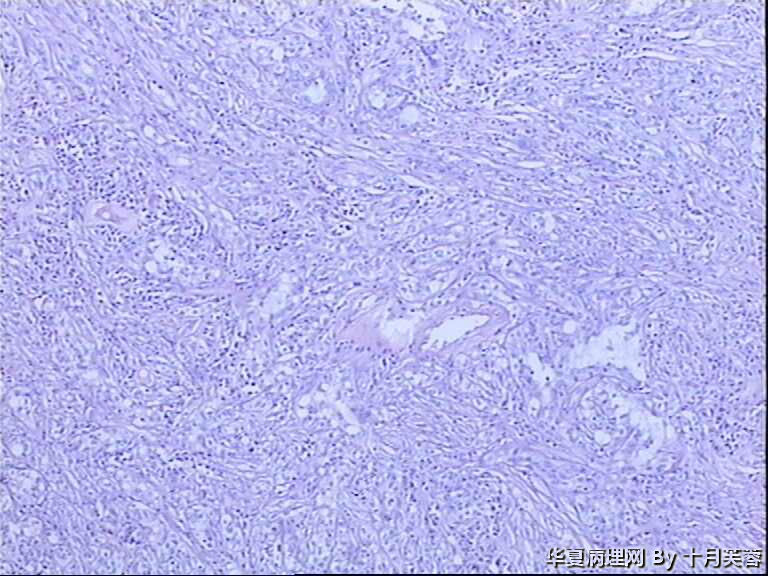

肾脏肿瘤

患者,女性,70岁,左肾实质内可见一肿物,大小4.3x3.5x3.5cm,切面灰白色,实性,质中。图10、11为淋巴结内转移病灶。

集合管癌

集合管癌。